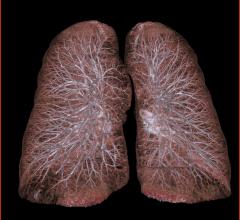

Previous evidence, including published National Lung Cancer Screening Trial (NLST) results, shows that computed tomography (CT) lung cancer screening significantly reduces lung cancer deaths in high risk patients*, and is appropriate, with careful patient selection and follow-up. This benefit significantly outweighs the comparatively modest rate of overdiagnosis noted in an article published online Dec. 9 in JAMA Internal Medicine. The American College of Radiology (ACR) will continue guideline and appropriateness criteria creation to support CT lung cancer screening programs across the country.

The American College of Radiology (ACR) and the Radiological Society of North America (RSNA) joined more than 100 medical societies in 57 countries around the world in celebrating the second annual International Day of Radiology (IDoR) on Nov. 8. IDoR 2013 focused on the important role lung imaging plays in the diagnosis and treatment of lung diseases, including the advent of computed tomography (CT) lung cancer screening.

Americans at increased odds of a potentially lethal lung cancer diagnosis may soon be able to seek out the most promising technology available to detect it early and ultimately have screening covered by insurance, including Medicare. The U.S. Preventive Services Task Force (USPSTF) recommended a high "B" rating for annual computed tomography (CT) scans for current and former smokers, aged 55 to 80, with a history of heavy smoking (two packs per day over 20 years or one pack a day over 30 years).